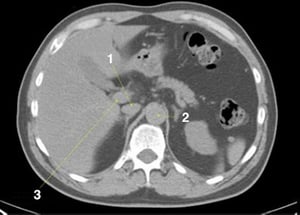

CT-Scan von Abdomen und Becken mit normaler Anatomie ohne Kontrastmittel (Folie 6)

1 = V. cava inferior; 2 = Aorta; 3 = Pfortader.

© Springer Science+Business Media